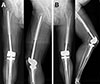

In competing-risk regression analysis using the Fine–Gray model, no mechanical variable was statistically significantly associated with the risk of mechanical failure (Table 3). Length of defect, stem diameter, and fixation length showed no statistically significant association with mechanical failure (all p > 0.05). Representative radiographs of mechanical failure due to aseptic loosening of a cemented custom-made distal femoral megaprosthesis are shown in Figure 4.

Figure 4 Representative radiographs of cemented custom-made distal femoral megaprosthetic reconstruction after tumor resection. (A) Patient following resection of a conventional grade 2 chondrosarcoma with a 20 cm distal femoral defect reconstructed using a cemented custom-made distal femoral replacement (stem diameter 14 mm, fixation length 21 cm). (B) Patient with malignant epithelioid hemangioendothelioma treated with distal femoral resection of 14 cm and reconstruction using a cemented custom-made megaprosthesis (stem diameter 16 mm, fixation length 17 cm), demonstrating aseptic loosening 6 years after implantation. |